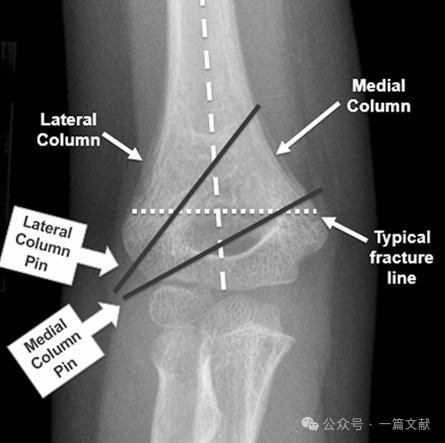

I. Bony Anatomy: The distal humerus is composed of a medial column and a lateral column, which are connected by the articular segment. During fracture, the medial and lateral columns are prone to displacement.

The medial and lateral columns are connected by a thin bone fragment at the olecranon fossa.

K-Wire Fixation Techniques:

* Cross Pinning (Medial & Lateral):

* Indications for Medial Pinning Include:

* Medial comminution.

* Proximal medial to distal lateral oblique fracture pattern (reverse oblique fracture).

* Intra-articular variant fractures. (As shown in the figure).

* Ideal Pin Placement Requirements: Use 1.5-2 mm K-wires. Pins should engage the medial and lateral columns with a divergent pattern. Greater separation between pins increases stability. As shown in the figure, pin configurations for Type 2A, 2B, and 3 fractures.

* Achieve wide separation at the fracture site.

* Pins should follow the metaphyseal flare to capture the lateral column.

* Laterally placed pins can be used to capture the medial column.

* Pin tips should engage the distal fragment just proximal to the fracture line.